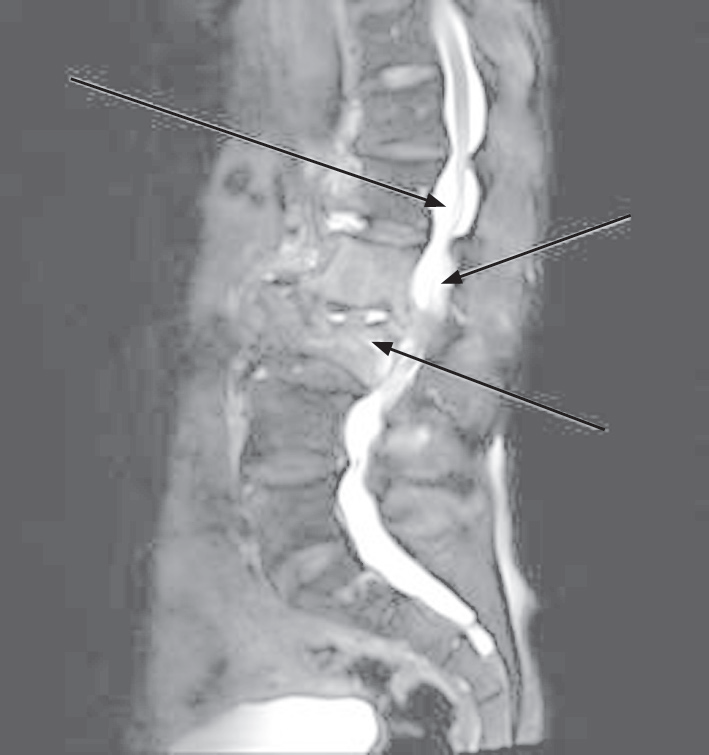

2.5 典型案例的影像特征

患者女,52 岁,主诉持续腰椎疼痛 7 个月,近 1 周疼痛显著加剧,已对日常生活活动造成明显影响。MSCT 影像显示,L2 及 L3 椎体存在明确骨质破坏征象,且破坏区域的骨质密度异常增高,尤以 L2 椎体破坏最显著;同时,L2 与 L3 间的椎间隙明显变窄;L1~L3 椎体的右侧区域出现条带状稍低密度影,边缘界限清晰,提示可能存在特定的病理改变或组织异常。MRI 影像显示,L2 和 L3 椎体均出现不同程度的扁形变化,椎体骨质出现破损,以 L2 椎体比较显著;L2 和 L3 椎体右方出现斑片状稍长 T1WI、T2WI 信号,L2~L3 椎间隙变窄。从影像结果变化可看出,MSCT 与 MRI 对腰椎结核的影像学诊断结果比较趋同,但具体细节上 MSCT 的纵深变化较优,MRI 的横向变化较优。典型案例的影像特征见图 1。

注:(a)为 MRI 影像,箭头所示位置为骨质破坏区域;(b)为MSCT 影像,箭头所示位置为骨质密度增高区域

图 1 典型案例的影像特征